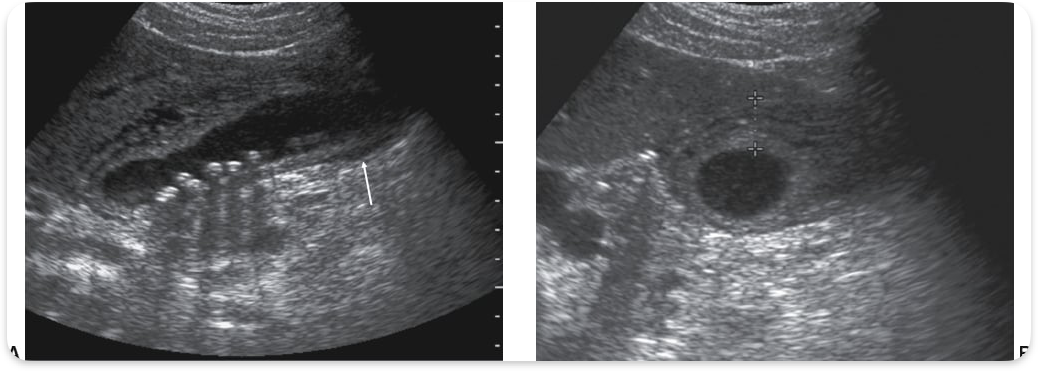

Adenomyomatosis

Thickened wall, diverticuli (rokitansky Aschoff sinuses)

Rokitansky Aschoff sinuses

Pockets in gallbladder wall containing cholesterol crystals, causing comet-tail artifact. (Adenomyomatosis)